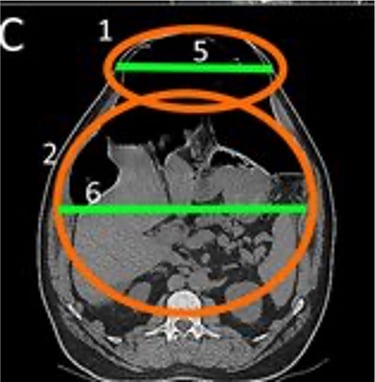

Realizamos una Tomografía Axial Computarizada con reconstrucción en 3D de la Pared Abdominal y de la hernia, cuando corroboramos que todo está listo, el siguiente paso es elegir el tipo de malla quirúrgica a colocar en la cirugía.